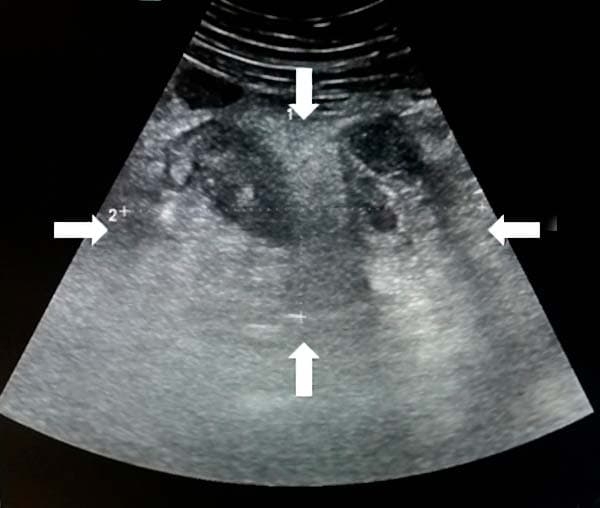

Из протокола УЗИ: «В правой подвздошной области визуализируется инфильтрат, определяется свободная жидкость межпетельно» (см. рис. 17).

Рисунок 17. УЗ-визуализация инфильтрата.

Из протокола операции: «Во всех отделах брюшной полости гной. Петли тонкой кишки раздуты, гиперемированы, отечны. В правой подвздошной ямке инфильтрат, состоящий из купола слепой кишки, червеобразного отростка, петли тонкой кишки, париетальной брюшины» (см. рис. 18).

Рисунок 18. Вскрытие абсцесса при разъединении инфильтрата в правой подвздошной области.